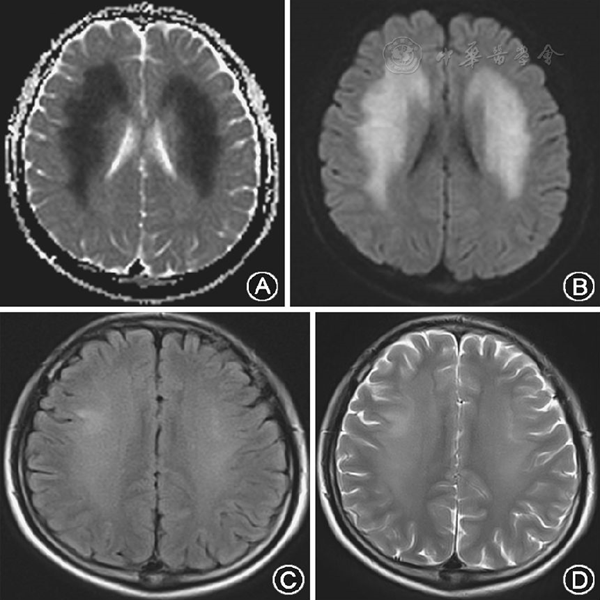

急转重症监护病房进行治疗,于2014年12月28日14:44时查头颅MRI(图1)显示急性脑水肿表现,DWI、T2、FLAIR显示额、颞、顶叶大片状高信号,表观弥散系数图像上病灶处信号减低,由头颅MRI表现明确诊断为透析性脑病,可除外脑干梗死。予呋塞米脱水及持续床旁血滤等治疗,2014年12月28日19:00时患者意识转为正常,四肢抽搐、双眼上窜发作未再反复,因患者经济条件差,未复查头颅MRI,患者定期于我院肾病科透析治疗,未再出现意识模糊、四肢抽搐、双眼上窜发作。

图1患者2014年12月28日影像学资料。A:表观扩散系数图像示两侧额、颞、顶叶脑白质区对称性大片状低信号;B:头颅DWI示病灶区成对称性大片状高信号区;C:FLAIR示两侧额、顶叶片状不均匀稍高信号;D:T2加权像示两侧额、顶叶片状不均匀稍高信号